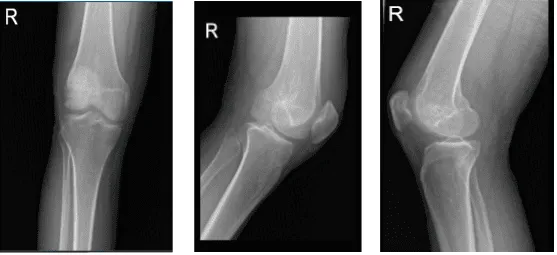

Rayos X de rodilla derecha, vistas AP laterales y oblicuas 3